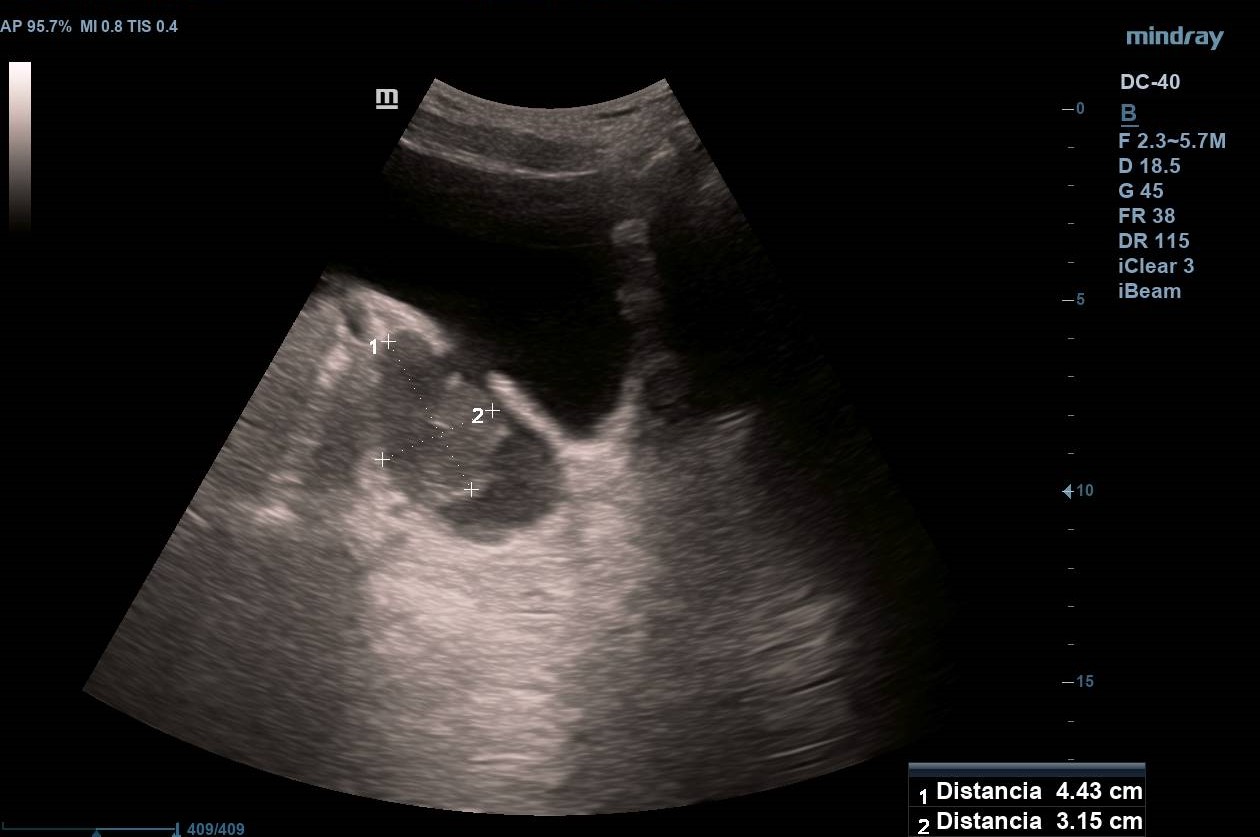

Divertículo vesical de 6 cm de diámetro en cuyo interior se observa masa homogénea de 4,43 x 3,15 cm que no capta Doppler y que parece depender de pared diverticular. Próstata homogénea de 37 cm3 (Imagen 1).